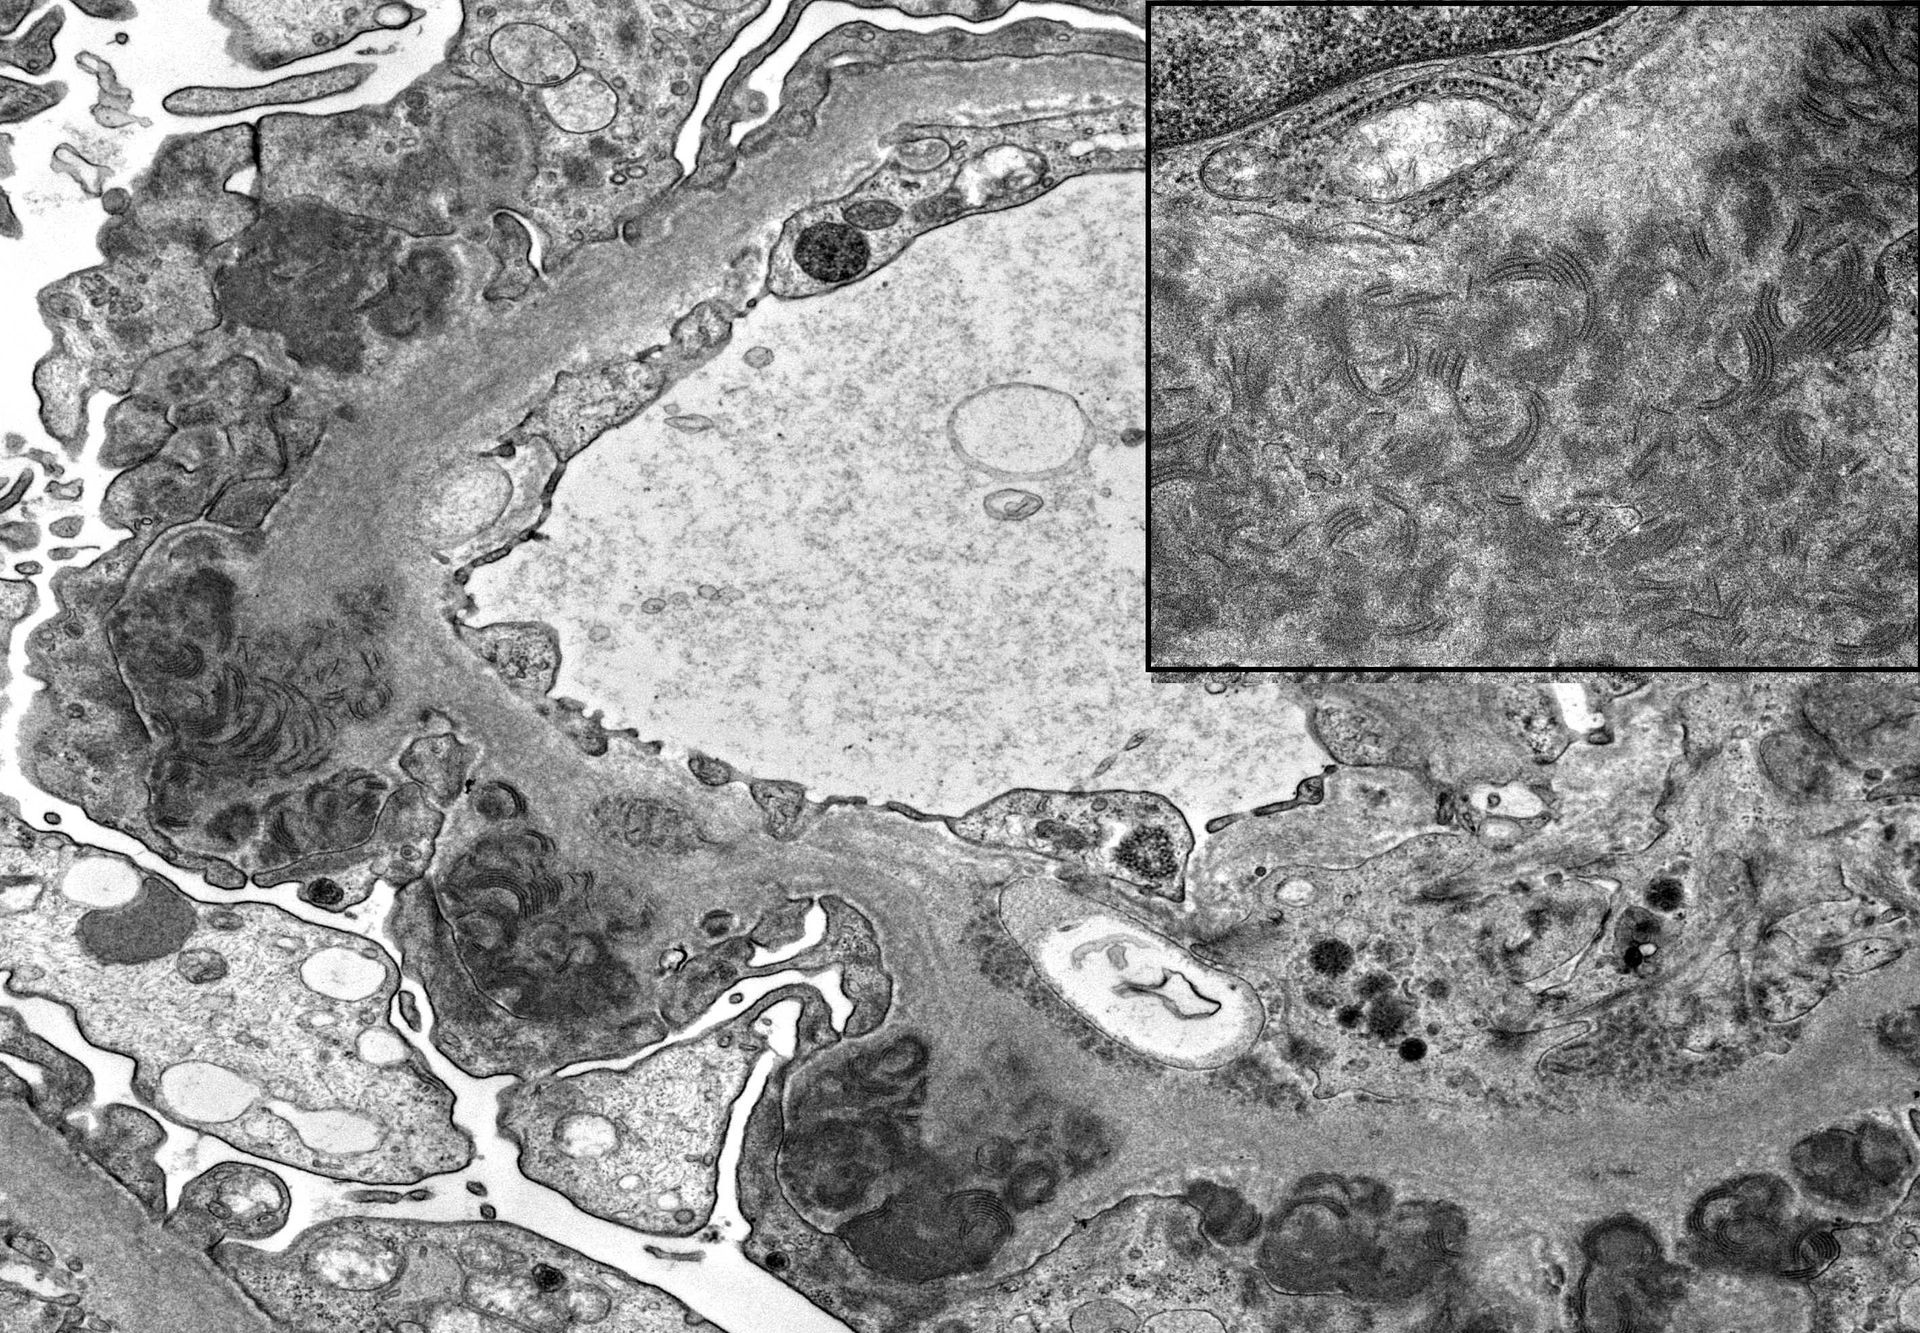

- ਡਾਇਗਨੌਸਟਿਕ ਅਰਧ-ਪਤਲਾ ਰਾਲ ਭਾਗ

- ਅਨੁਕੂਲ ਅਤੇ ਉਪ-ਅਨੁਕੂਲ ਰੰਗਾਈ ਦਿਖਾਉਣ ਵਾਲੇ ਰੰਗ ਚਿੱਤਰਾਂ ਦੀ ਔਨਲਾਈਨ ਲਾਇਬ੍ਰੇਰੀ